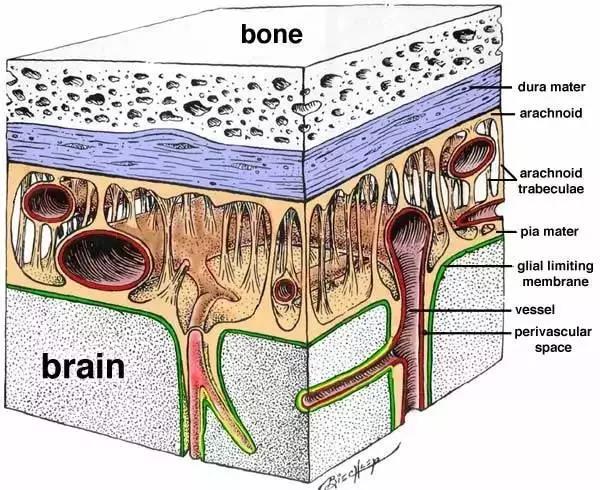

你的頭骨下面,又是一大堆東西,之后才是你的大腦:

在你的頭骨下面,大腦周圍有三個膜,將大腦環繞:

在外面,有硬腦膜,堅固耐用,防水。硬腦膜與顱骨齊平。我聽到有人說,大腦中沒有疼痛感覺區,但硬腦膜實際上能感覺疼痛,且和你的面部肌膚一樣敏感,硬膜上的壓力或挫傷往往造成了人們嚴重的頭痛。

然后下面是蛛網膜,這是一層皮膚,然后是帶有彈性的纖維的開放空間。我一直以為我的大腦只是漫無目的地漂在我大腦中的某種液體里,但實際上,腦外和顱骨內壁之間的唯一真正的空間差距是這個蛛網膜。這些纖維穩定了大腦的位置,因此不能動作太大,他們充當減震器,當你的頭撞到東西。這個區域充滿了脊髓液。

最后,是軟腦膜,和腦外融合的很精巧的皮膚層。你知道,當你看到一個大腦,它總是覆蓋著惡心的血管。但這些并不是真正在大腦的表面上,它們埋設在里面。

從左到右是皮膚(粉紅色),然后是兩個頭皮層,然后是頭骨,然后是硬腦膜,蛛網膜,最右邊是只由軟腦膜覆蓋的大腦。

你的頭骨下面,又是一大堆東西,之后才是你的大腦:

在你的頭骨下面,大腦周圍有三個膜,將大腦環繞:

在外面,有硬腦膜,堅固耐用,防水。硬腦膜與顱骨齊平。我聽到有人說,大腦中沒有疼痛感覺區,但硬腦膜實際上能感覺疼痛,且和你的面部肌膚一樣敏感,硬膜上的壓力或挫傷往往造成了人們嚴重的頭痛。

然后下面是蛛網膜,這是一層皮膚,然后是帶有彈性的纖維的開放空間。我一直以為我的大腦只是漫無目的地漂在我大腦中的某種液體里,但實際上,腦外和顱骨內壁之間的唯一真正的空間差距是這個蛛網膜。這些纖維穩定了大腦的位置,因此不能動作太大,他們充當減震器,當你的頭撞到東西。這個區域充滿了脊髓液。

最后,是軟腦膜,和腦外融合的很精巧的皮膚層。你知道,當你看到一個大腦,它總是覆蓋著惡心的血管。但這些并不是真正在大腦的表面上,它們埋設在里面。

從左到右是皮膚(粉紅色),然后是兩個頭皮層,然后是頭骨,然后是硬腦膜,蛛網膜,最右邊是只由軟腦膜覆蓋的大腦。